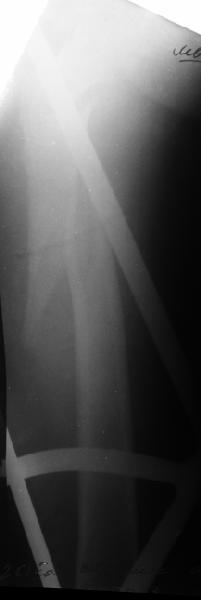

Наш туземный подход - flat radiolucent table и спицевой дистрактор.

Мы обычно проводим спицу ближе к заднему кортексу - иногда бывает, гвоздь смещается кзади, за фрагменты, особено при многооскольчатых переломах...